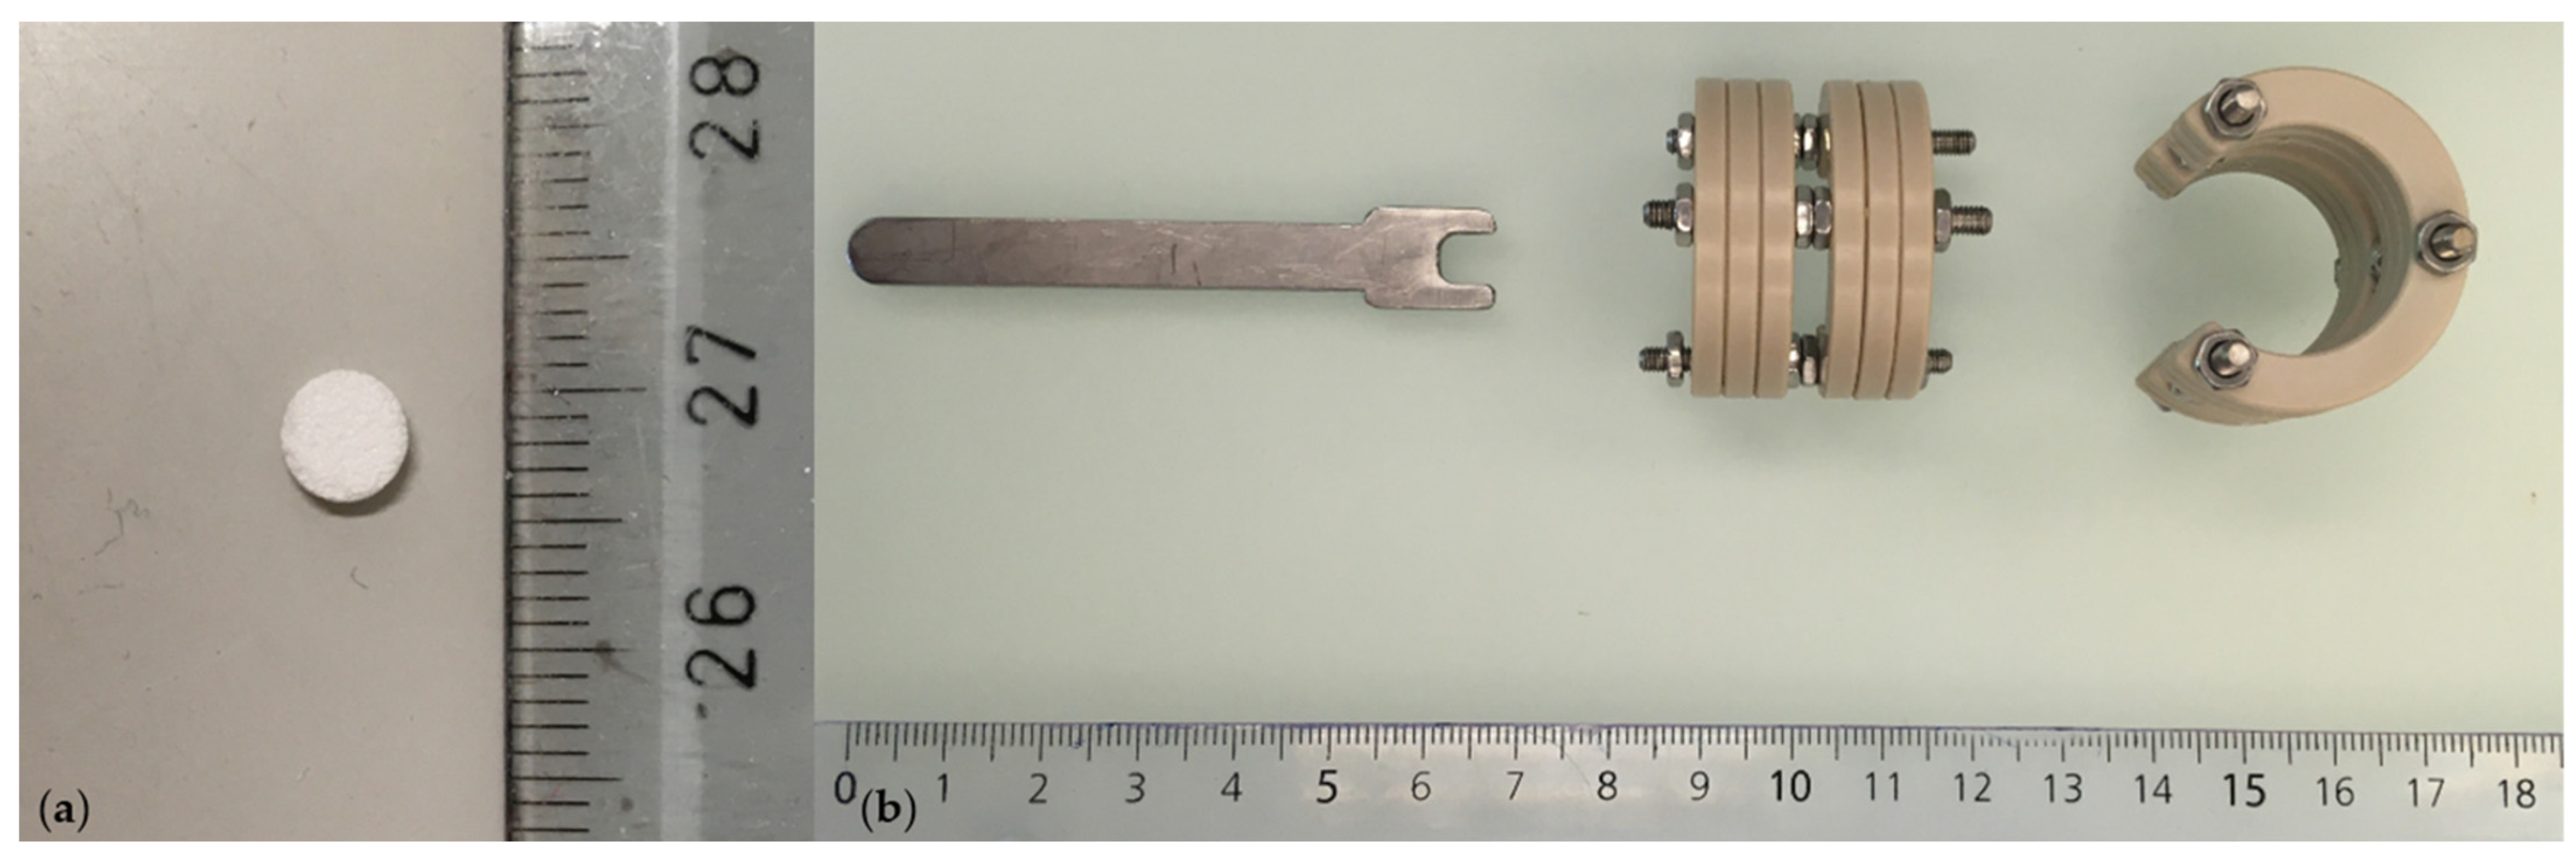

- β-TCP carrier, ∅ 0.5 mm, h = 1.5 mm, 75% porosity (produced by Prof Marc Bohner, Robert Mathys Foundation, Bettlach, Switzerland) (Figure 2a).

- Customized external ring fixator (Urs Rohrer, SITEM, Inselspital, University Hospital Bern, Bern, Switzerland) (Figure 2b).

- Customized hex wrench (Urs Rohrer, ARTORG Center, Inselspital, University Hospital Bern, Bern, Switzerland) (Figure 2b).